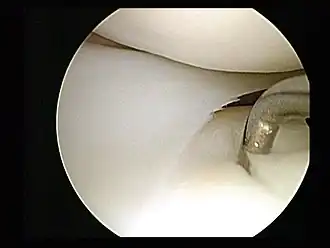

Artroscopie

Artroscopie is een procedure uit de minimaal-invasieve chirurgie, die het inwendige van een gewricht inspecteert of opereert, door middel van een artroscoop, een type van endoscoop die in het gewricht wordt gebracht via een kleine insnijding. De populairste gewrichten voor deze methode van onderzoek (en soms behandeling) zijn de knie en de schouder. Heupartroscopie wordt steeds vaker uitgevoerd, bijvoorbeeld om patiënten met heupimpingement te behandelen.